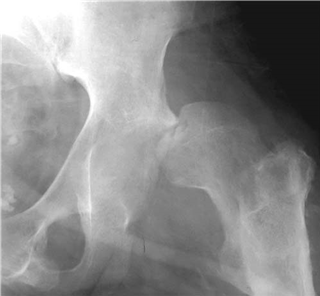

What does this radiograph show you and what would your initial management in the emergency department be?

This is an AP radiograph of the left hip showing a posterior dislocation. There is an associated impacted fracture of the femoral head on the posterior acetabular wall. This is a high-energy injury and with a high probability of other injuries. I would therefore perform a full ATLS-type review. I would assess and document the neurovascular status of the limb and provide adequate analgesia. I would liaise with theatres and seek the advice from my local pelvic specialist centre.